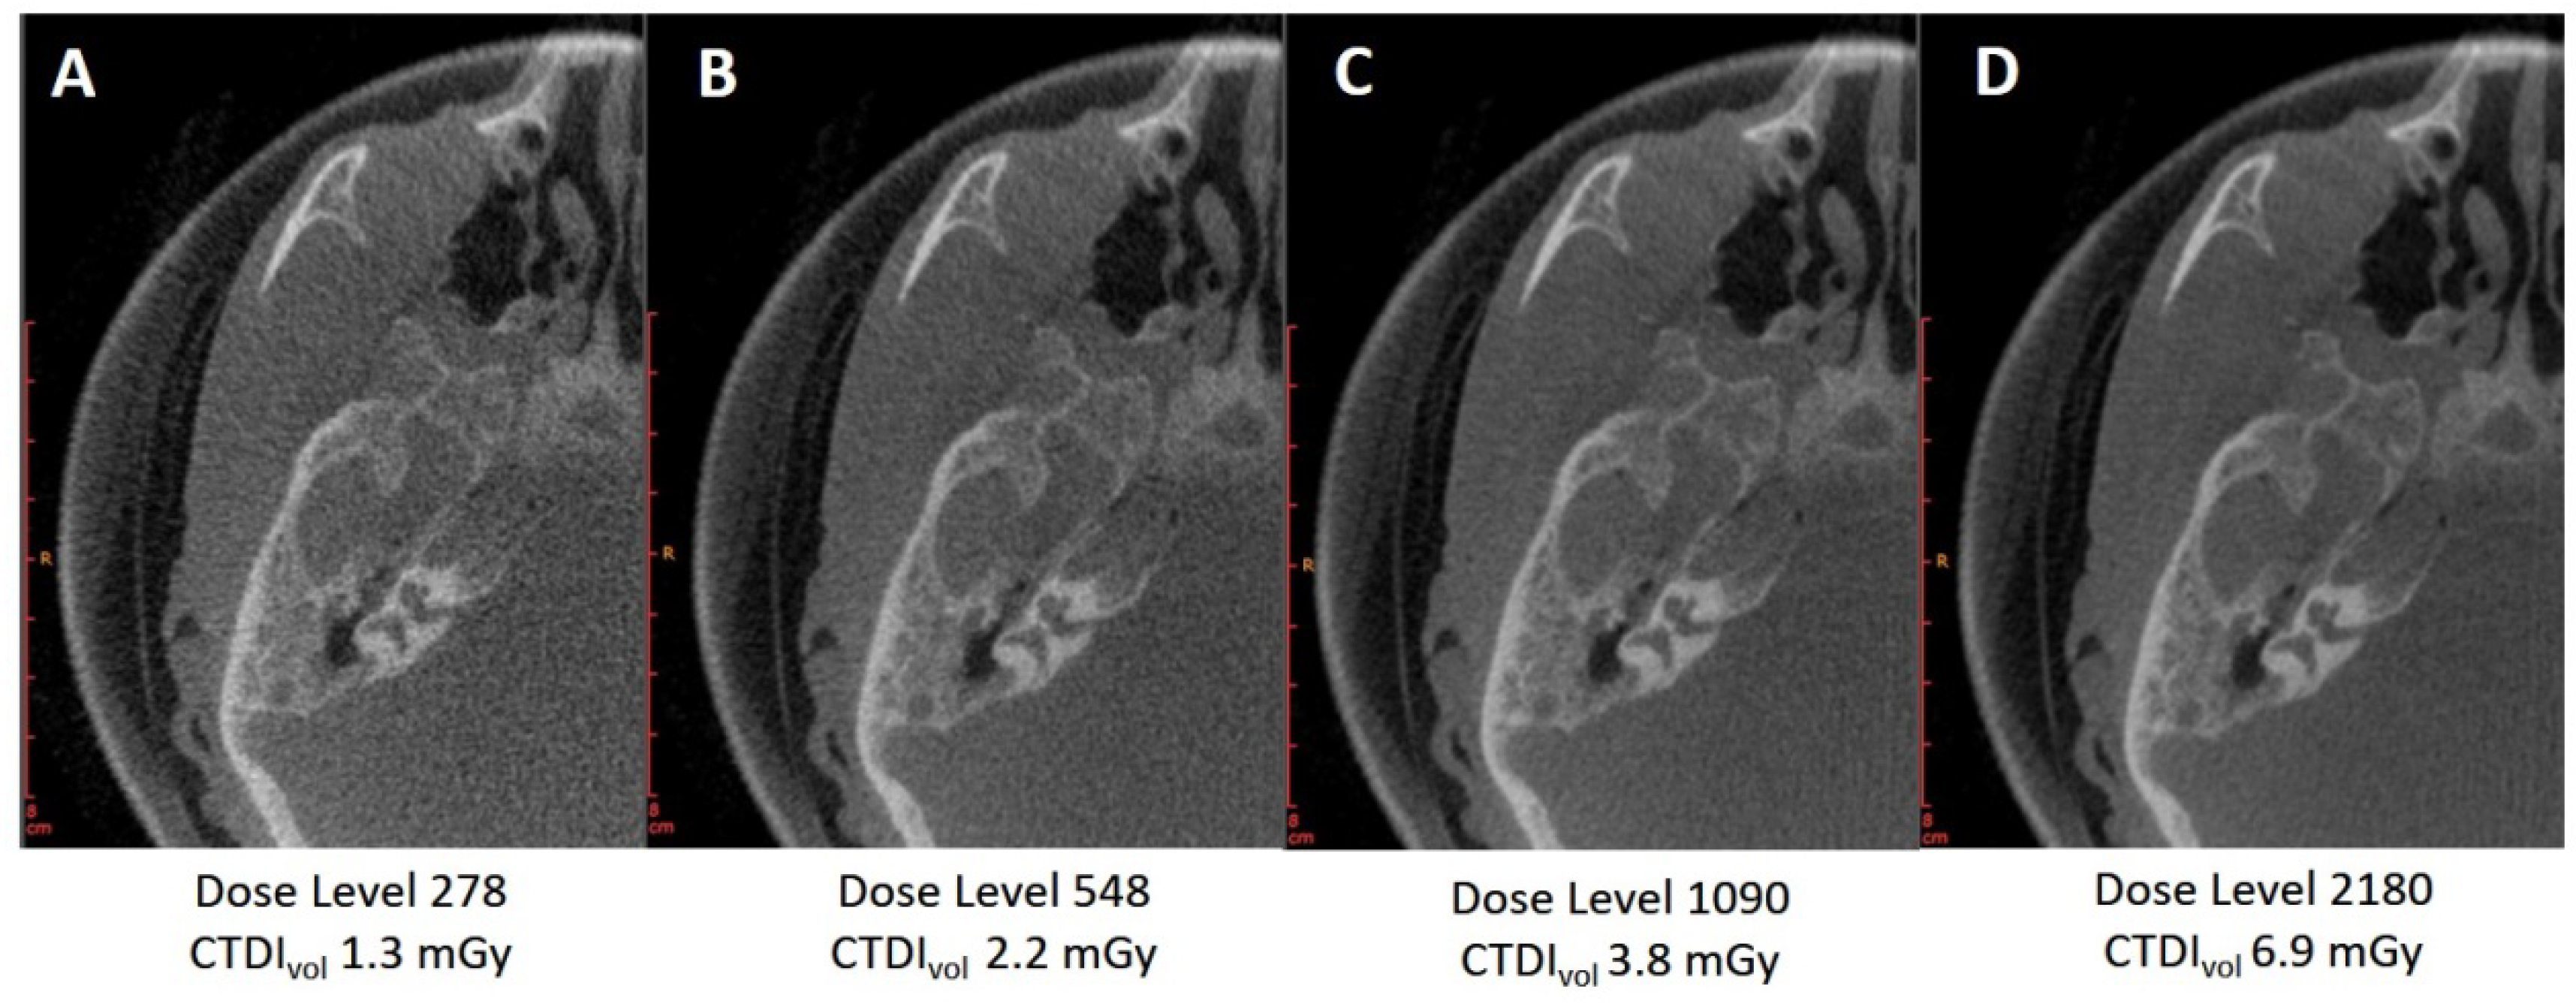

3.1.1. Variation of Tube Voltage

3.2.1. Pre-Filtration with 0.2 vs. 0.3 mm Copper Filter

3.2.2. Pre-Filtration with 0.4 mm Tin Filter